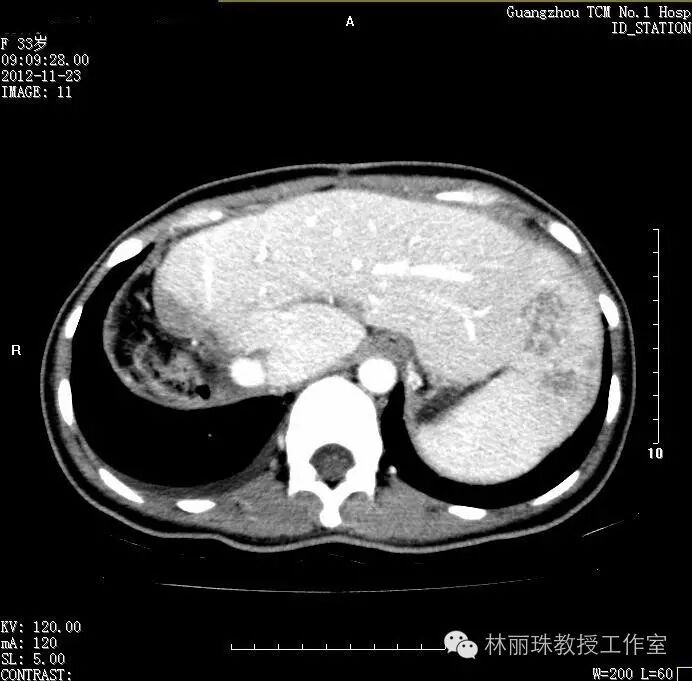

此后20121031日转至我院治疗,20121123日我院CT示肝内多发肿瘤转移。于1128日开始行GEMOX方案化疗7程,期间2013126日在我院CT引导下行经皮肝脏肿物I125放射性粒子植入术。出院后门诊中医药治疗,定期复查提示病情稳定。

20121123日我院CT示肝内多发肿物